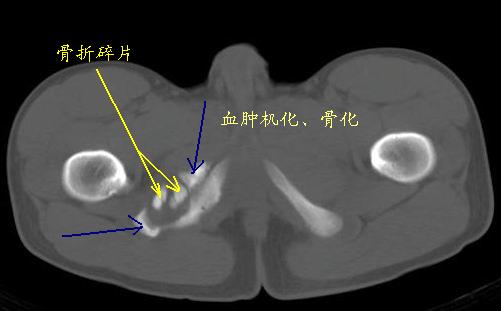

男性,15岁,半年前曾有做运动摔伤史,伤后左肢麻木,一天后恢复,两个月后因右臀部隐痛照片示右坐骨下骨性密度影,现复查见骨性影无明显改变。求助诊断!

骨折后的碎骨片。

坐骨撕脱性骨折伴骨化性肌炎

支持坐骨撕脱性骨折合并血肿机化、骨化。

坐骨陈旧性撕脱性粉碎性骨折伴骨痂形成.